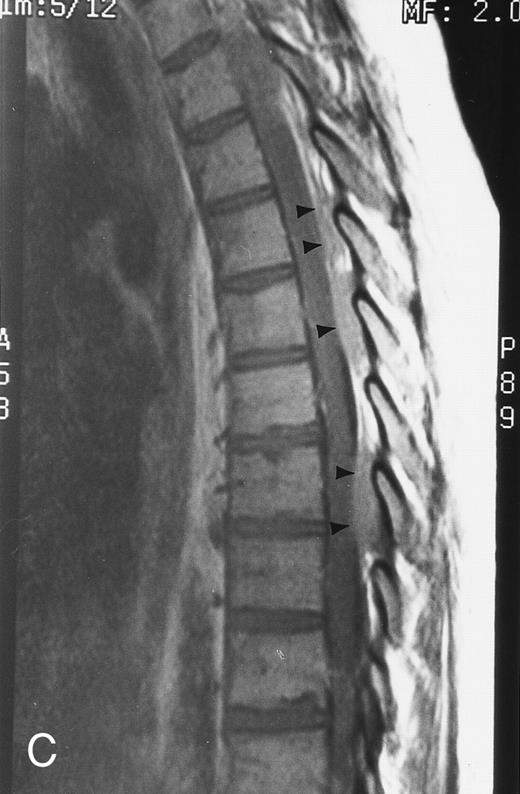

T1-weighted (500/11, TR/TE) sagittal MR images of the lumbosacral spine in a 45-year-old woman before (A) and 40 days after (B) bone marrow transplantation for multiple myeloma. There is a diffuse MR pattern of marrow involvement in (A) (bone marrow plasma cells, 50%; monoclonal protein, 6.0 g/dL). On the posttreatment image, there is definite reinstitution of fatty marrow in the spine and, in particular, around the basivertebral veins, in keeping with partial response to treatment (bone marrow plasma cells, 0.5%; monoclonal protein, 1.6 g/dL).